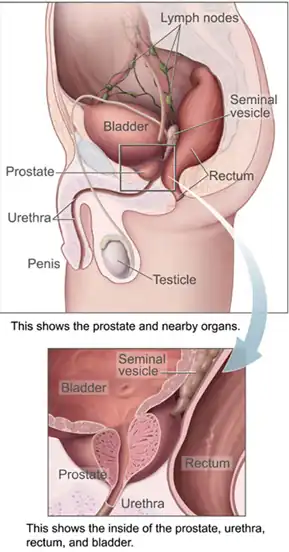

In males, the prostate gland lies outside the opening for the urethra. The middle lobe of the prostate causes an elevation in the mucous membrane behind the internal urethral orifice called the uvula of urinary bladder. The uvula can enlarge when the prostate becomes enlarged.

The bladder is located below the peritoneal cavity near the pelvic floor and behind the pubic symphysis. In males, it lies in front of the rectum, separated by the rectovesical pouch, and is supported by fibres of the levator ani and of the prostate gland. In females, it lies in front of the uterus, separated by the vesicouterine pouch, and is supported by the elevator ani and the upper part of the vagina.[10]